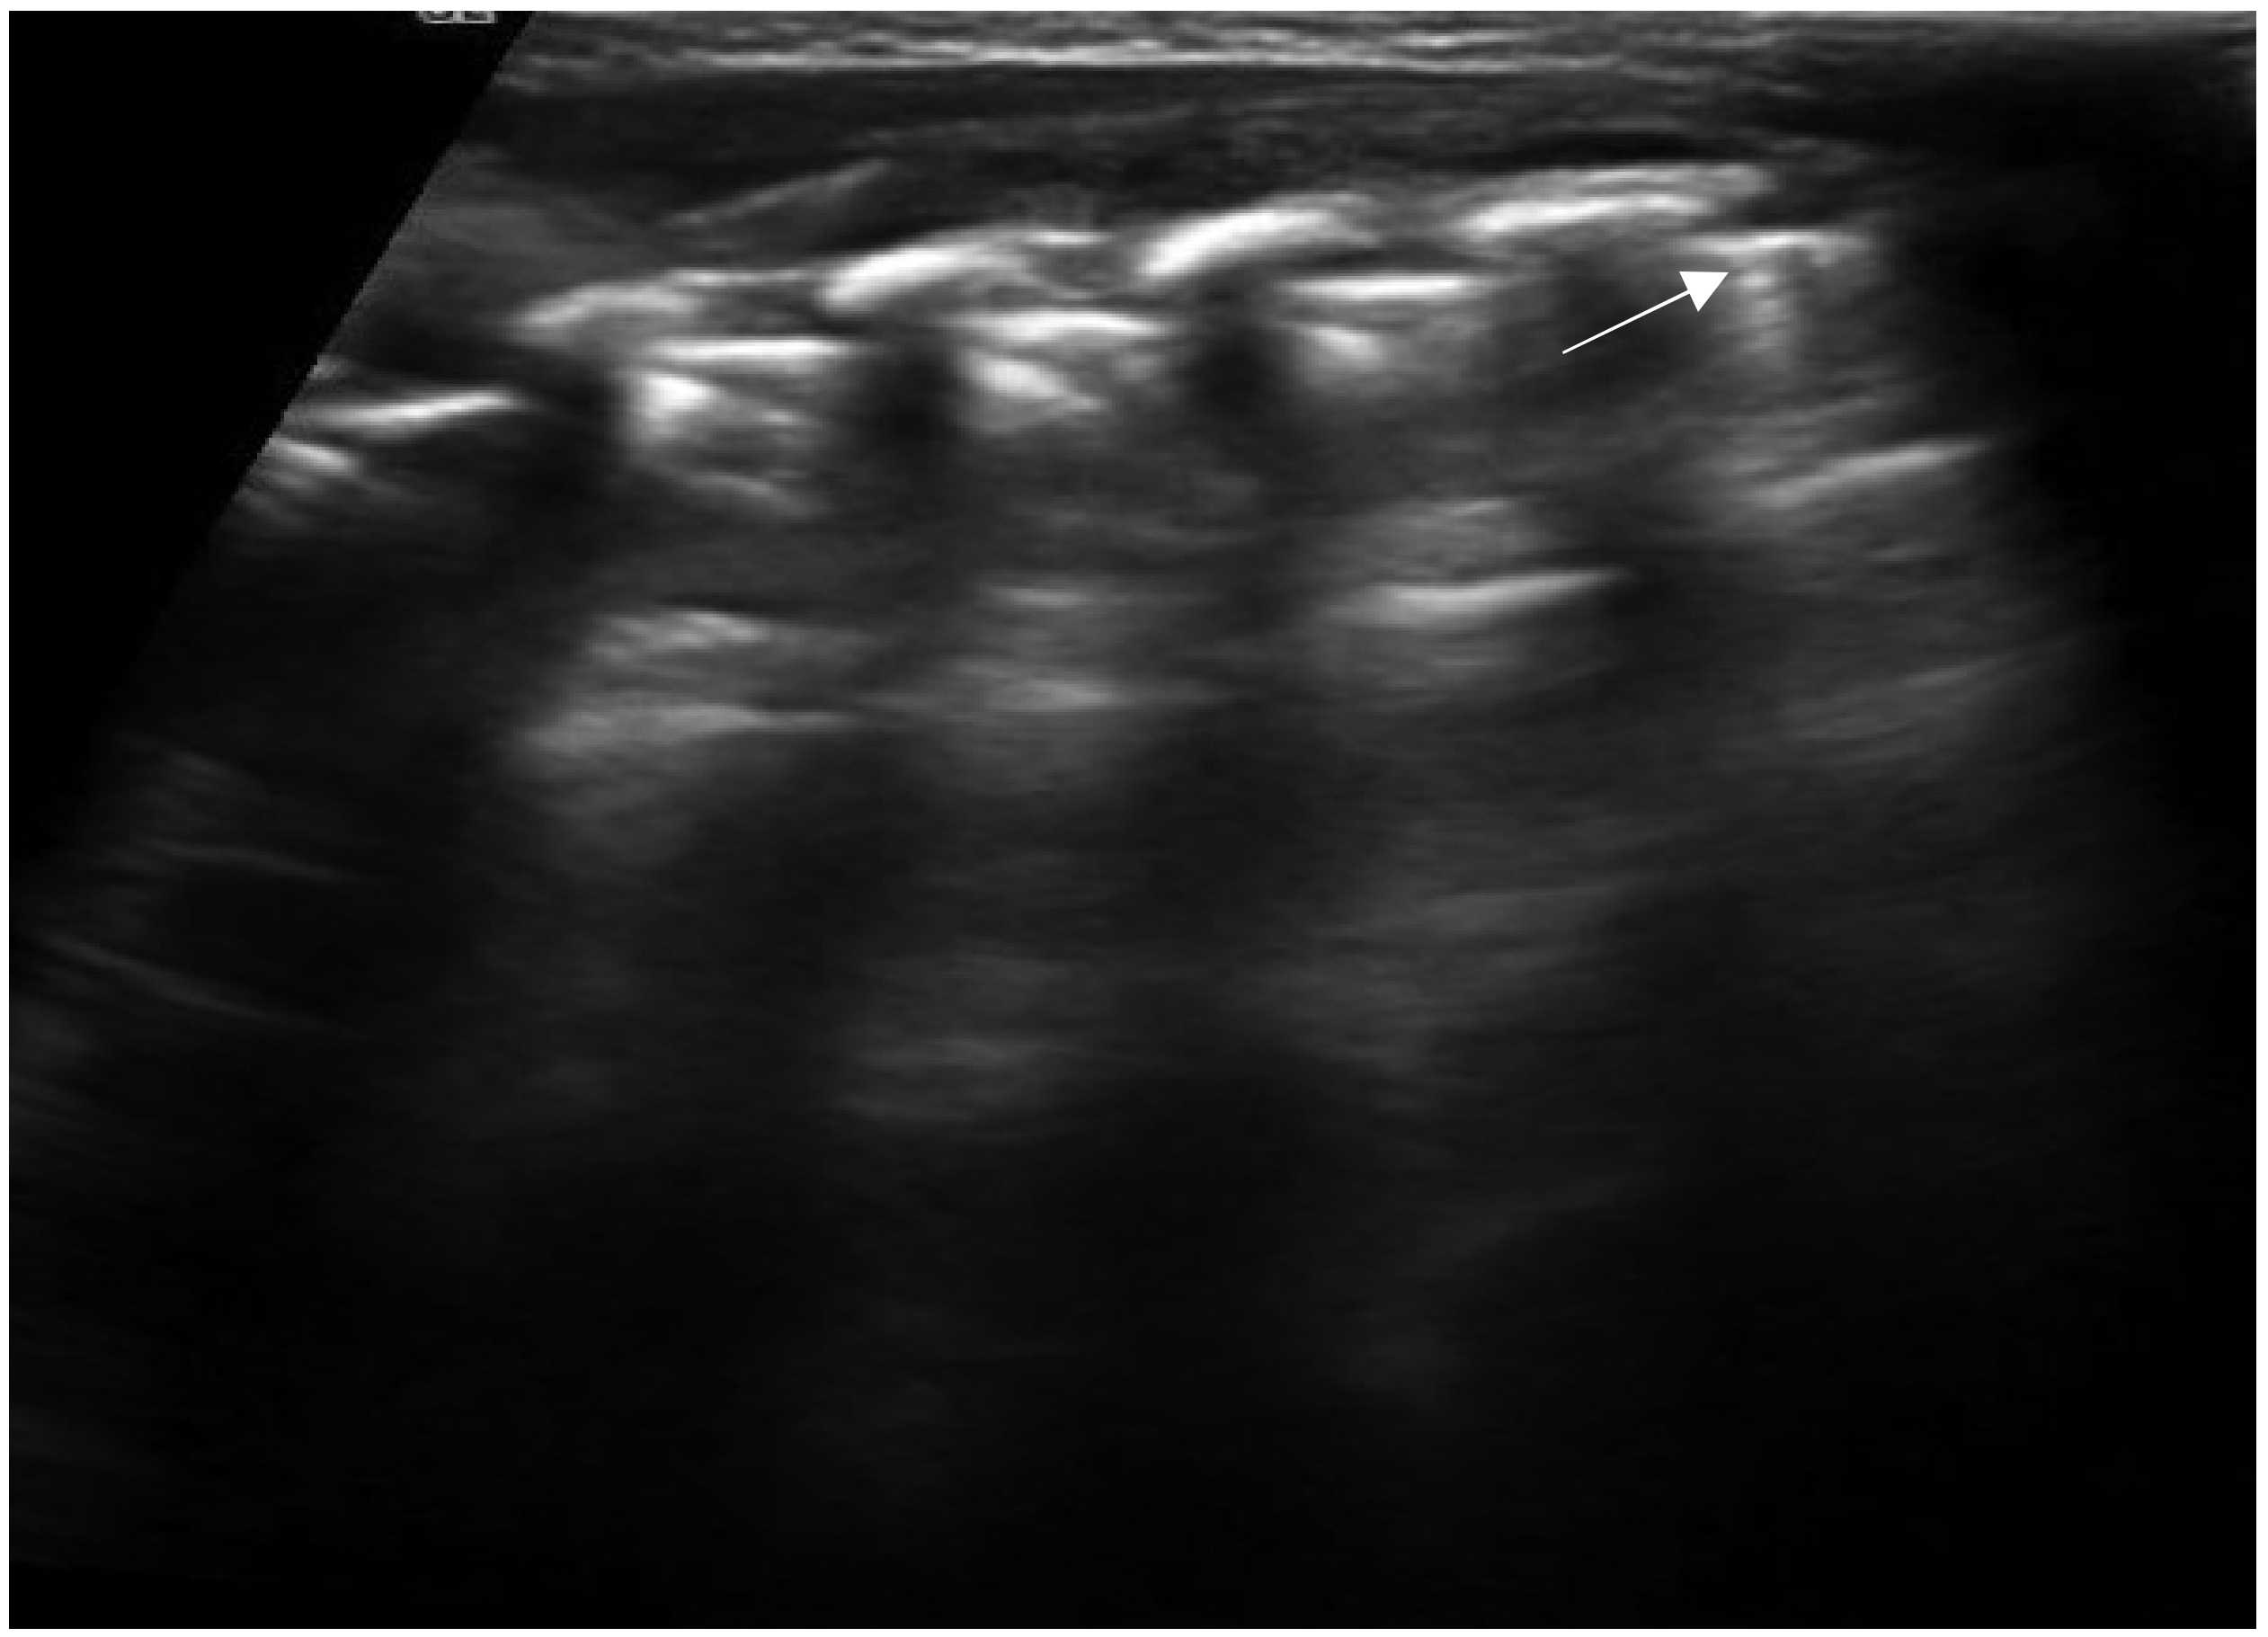

2. Technique and Equipment

3. Lung Ultrasound Findings in Healthy Subjects